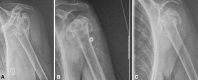

Background: Four-part fractures of the proximal humerus account for 3% of all humeral fractures and are regarded as the most difficult fractures to treat in the elderly. Various authors recommend nonoperative treatment or hemiarthroplasty, but the literature is unclear regarding which provides better quality of life and function.

Figures